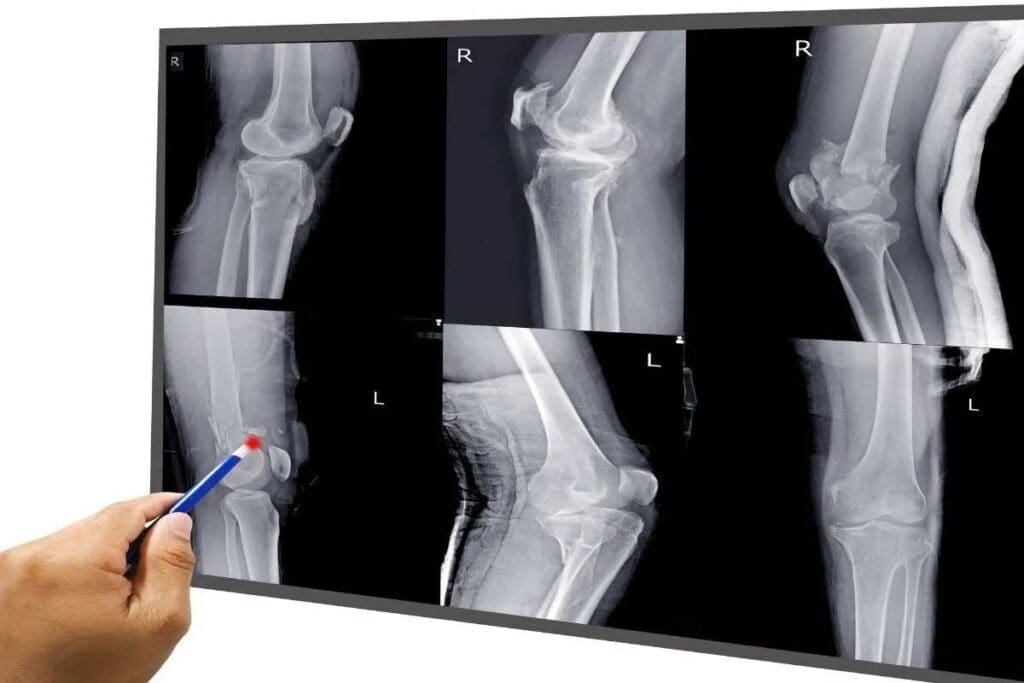

X-Ray Imaging: The First Line of Defense

X-ray imaging is often the first step in checking for bone fractures. It’s quick and easy to get. We use X-rays because they give us fast info about bone health.

How X-Rays Detect Broken Bones

X-rays use special radiation to show what’s inside our bodies. Bones show up white because they block the X-rays. Soft tissues are gray. A break in a bone looks like a dark line.

Advantages of X-Ray for Fracture Detection

X-rays are great for finding fractures. They work well for spotting breaks, misalignments, and changes in joint spaces. Their speed and easy access make them key in emergencies.

Limitations and Missed Fractures

Even with their benefits, X-rays have downsides. They might miss small or complex fractures, like stress or hairline ones. These can be hard to see with X-rays alone.